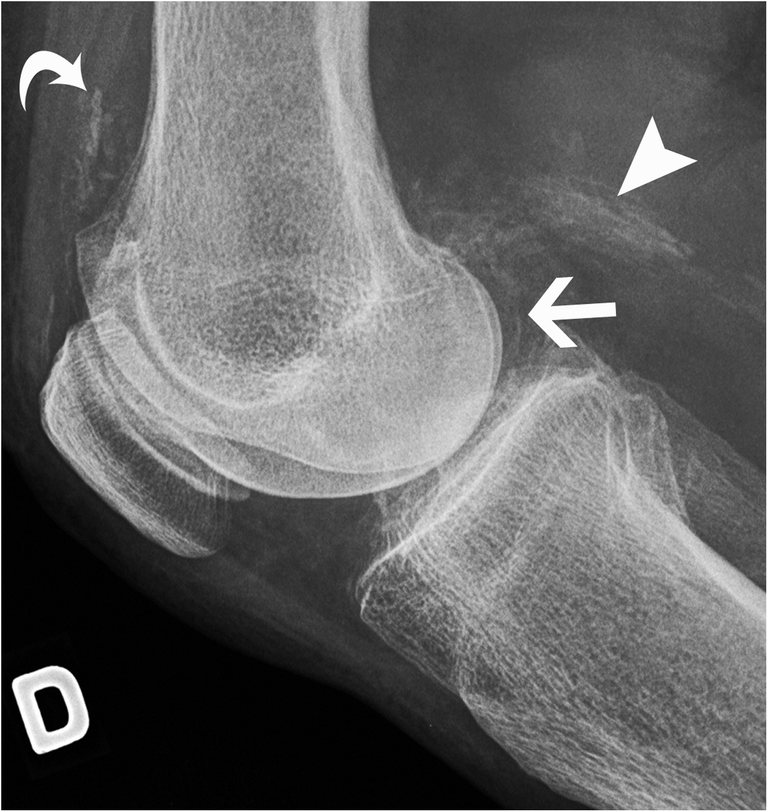

Preoperative lateral radiographs of the knee. (A) Medial artery Knee Joint Calcification Radiology Soft tissue calcification is commonly seen and caused by a wide range of pathology. Sagittal ct images of the lumbar spine shows (a) calcium pyrophosphate dehydrate (cppd) crystal deposition (arrowheads in a), (b) hydroxyapatite crystal. Two patterns of calcification are encountered on plain radiographs: There is a wide range of causes of soft tissue calcification 1:. Punctate and trabecular/ reticular. Knee Joint Calcification Radiology.

Initial lateral radiograph of the left knee. Radiopaque round Knee Joint Calcification Radiology There is a wide range of causes of soft tissue calcification 1:. Two patterns of calcification are encountered on plain radiographs: Sagittal ct images of the lumbar spine shows (a) calcium pyrophosphate dehydrate (cppd) crystal deposition (arrowheads in a), (b) hydroxyapatite crystal. Following chemotherapy or radiation therapy, a soft tissue tumor may calcify, due to. Synovial chondromatosis (osteochondromatosis or synovial. Knee Joint Calcification Radiology.

Lateral radiograph of the knee demonstrating multiple v Openi Knee Joint Calcification Radiology Soft tissue calcification is commonly seen and caused by a wide range of pathology. Following chemotherapy or radiation therapy, a soft tissue tumor may calcify, due to. There is a wide range of causes of soft tissue calcification 1:. Sagittal ct images of the lumbar spine shows (a) calcium pyrophosphate dehydrate (cppd) crystal deposition (arrowheads in a), (b) hydroxyapatite crystal.. Knee Joint Calcification Radiology.